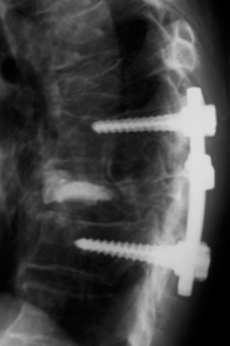

後方固定術を併用した椎体形成術

椎体形成術に椎体インストゥルメンテーションを併用した手術。

出典

img

1: 著者提供